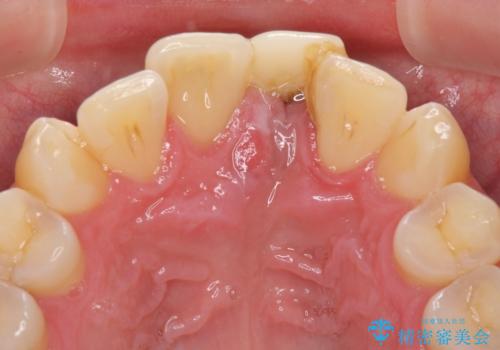

インプラントが唇側に埋入されており、セラミッククラウンの歯肉ラインが左右非対称となっていました。

仮歯は両サイドの歯と接着剤で止められており、接着が著しく変色していたため、セラミッククラウンが装着されて自然な口元となりました。